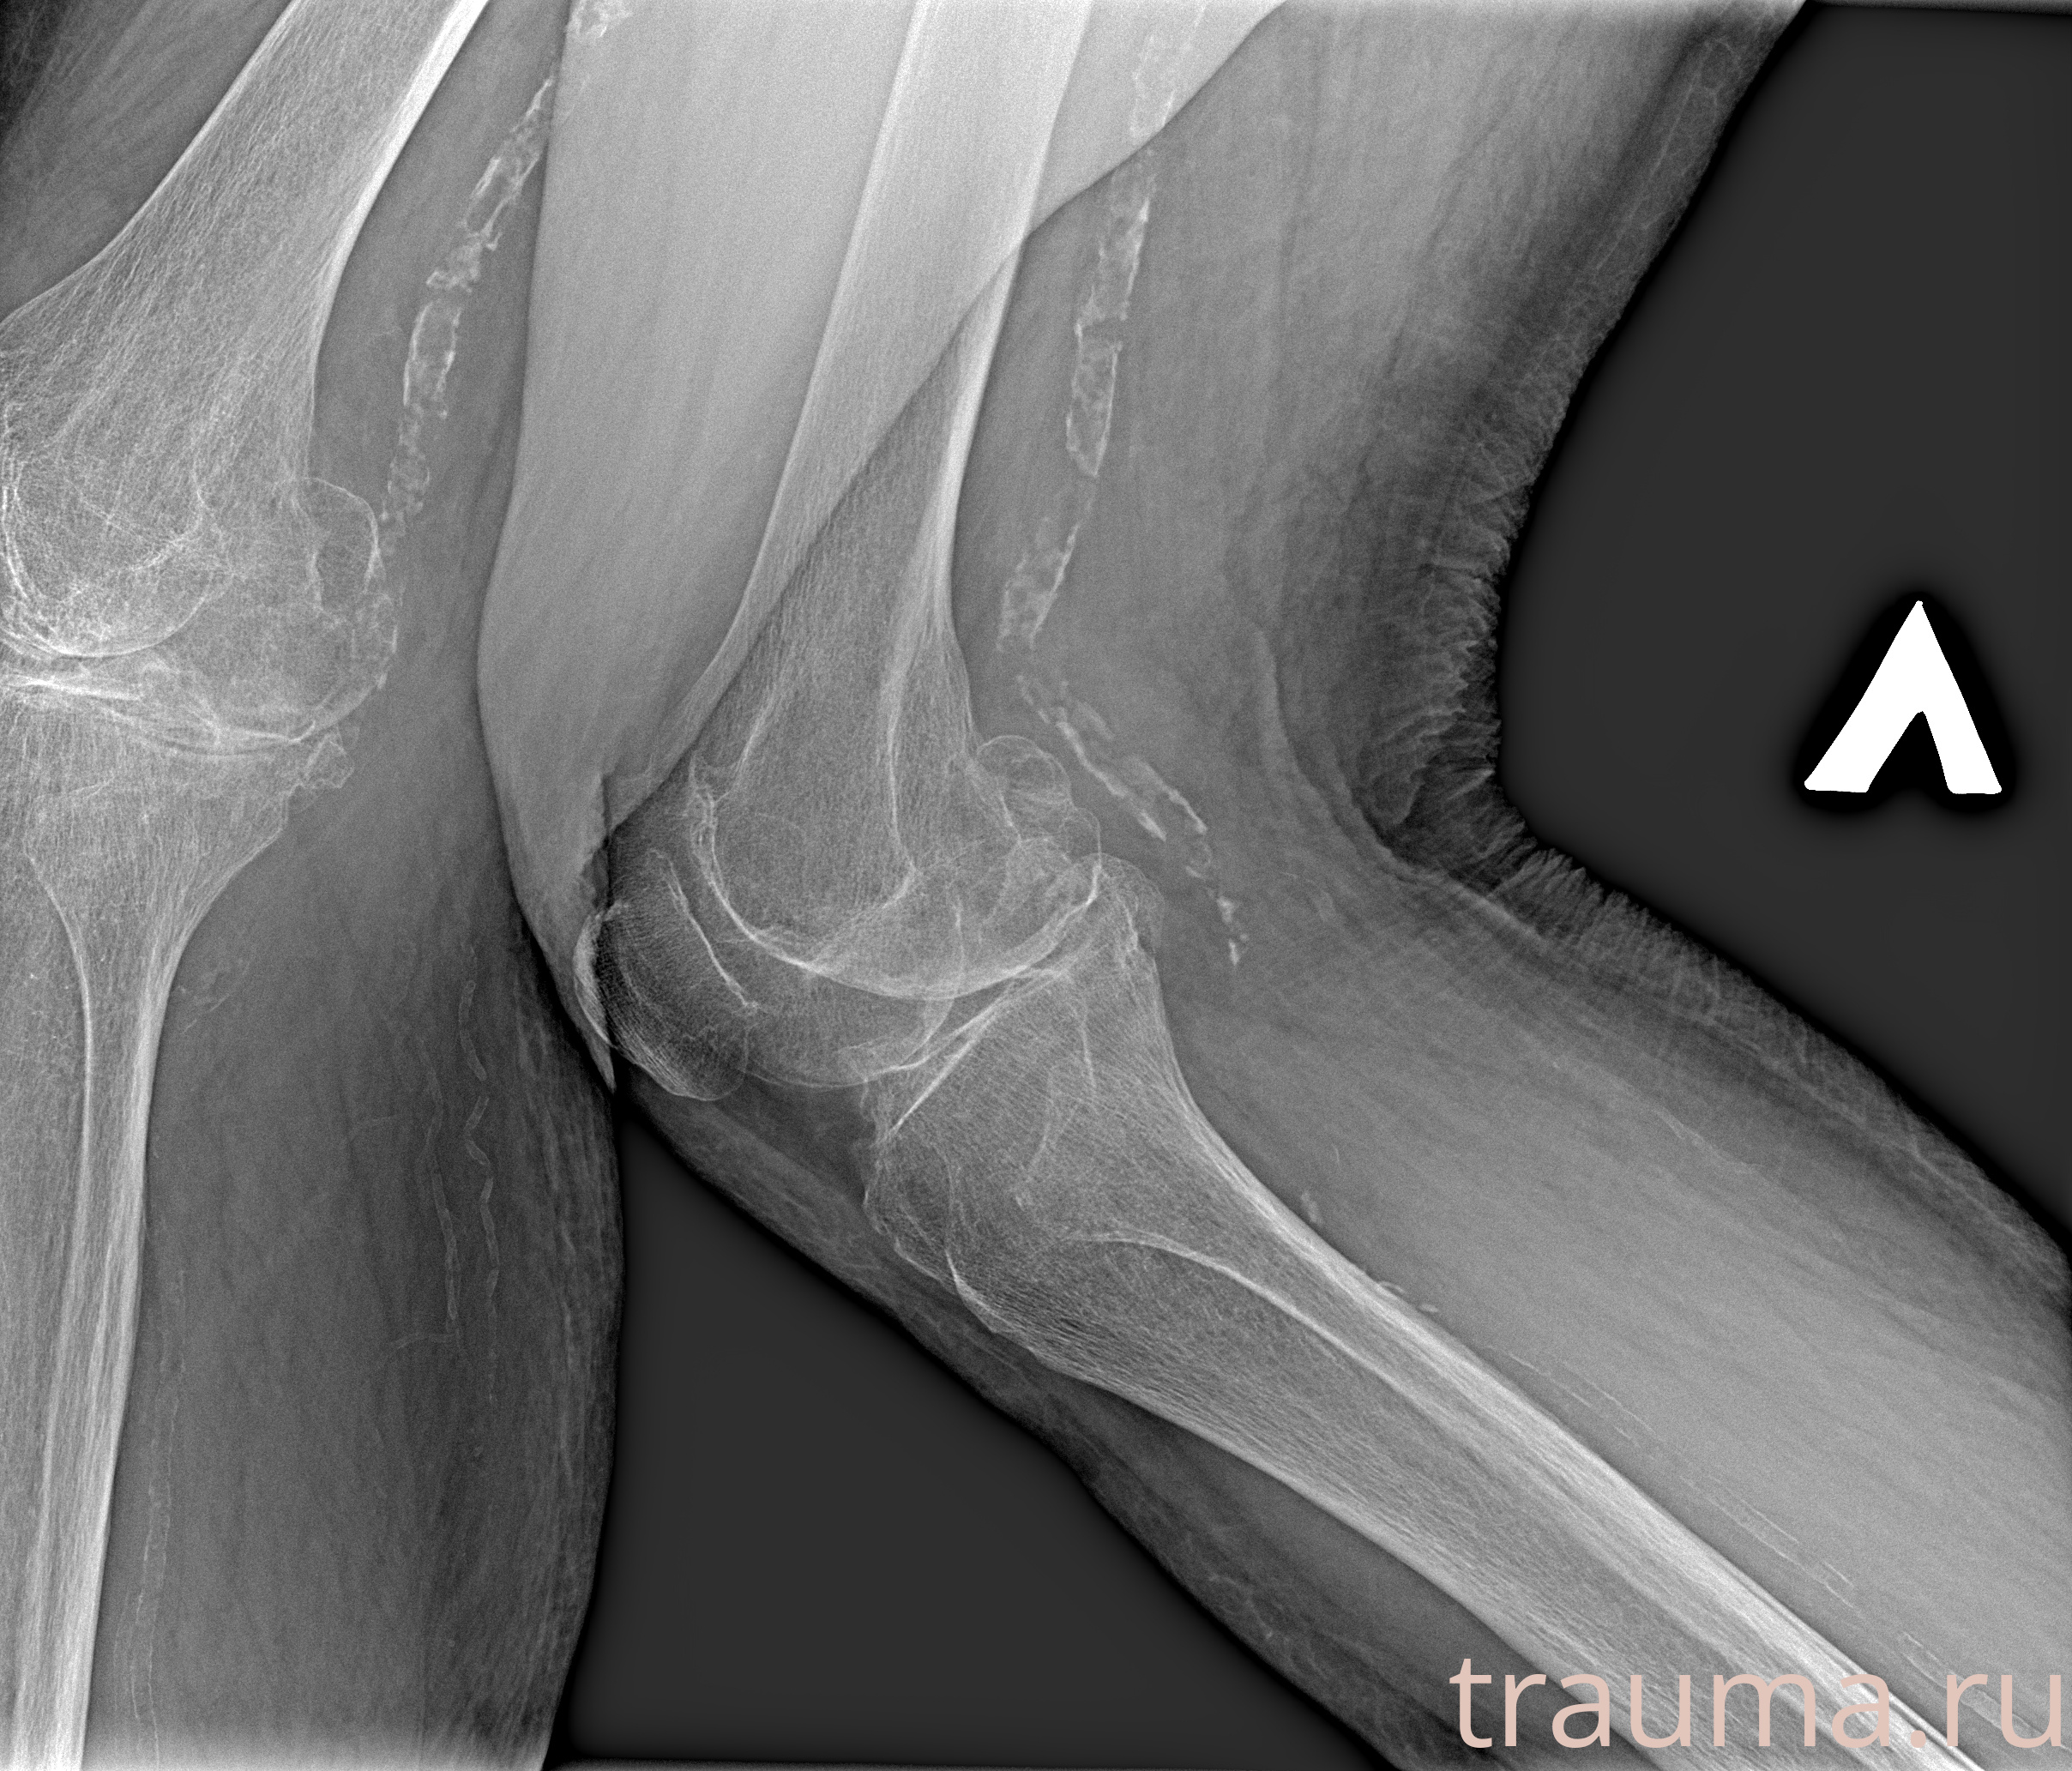

Рентген на дому: по вашему адресу приезжает врач-рентгенолог, травматолог-ортопед с мобильным рентгеновским аппаратом, проводит диагностику травмы или заболевания, делает необходимые рентгенограммы, дает рекомендации по дальнейшему лечению. Получить качественные снимки в домашних условиях возможно благодаря уникальной методике, разработанной МосРентген Центром для института  Склифосовского